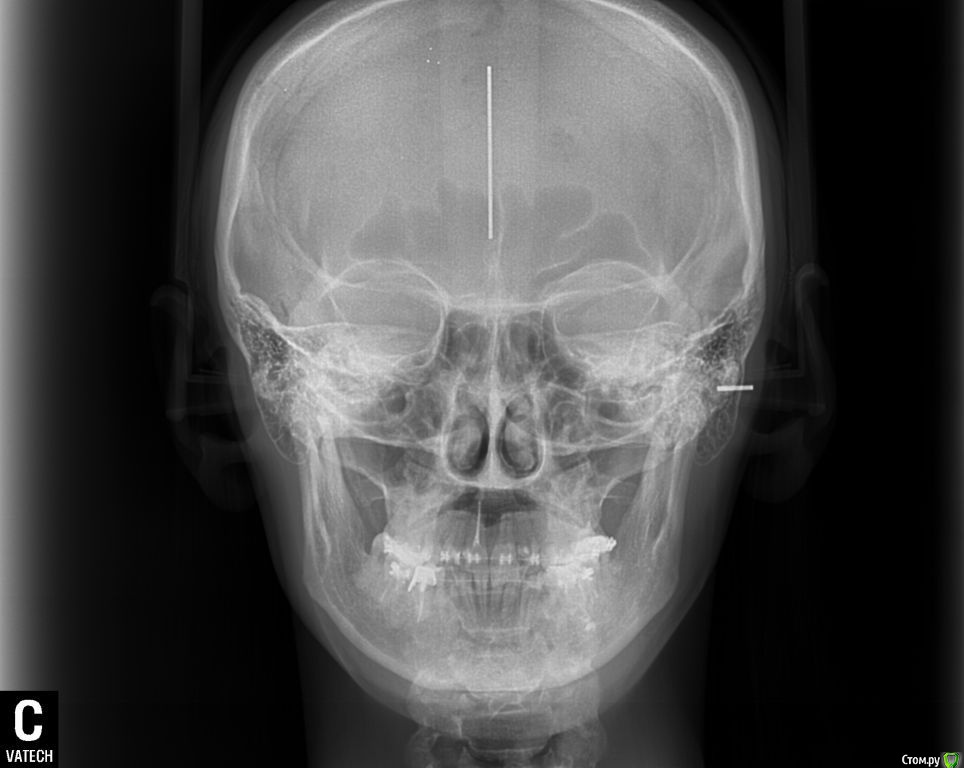

ol"ga Опубликовано 15 августа, 2015 Автор Поделиться Опубликовано 15 августа, 2015 (изменено) Вот еще кт левого и правого внчс, и фото улыбки Изменено 15 августа, 2015 пользователем ol"ga Ссылка на комментарий

Yana guapa Опубликовано 15 августа, 2015 Поделиться Опубликовано 15 августа, 2015 я не вижу у ВАс асимметрии лица, асимметрии верхней челюсти. А вот нижняя челюсть смещена влево, (это видно по ОПТГ и фото), вследствие чего произошло смещение дискав таких случаях обычно1. выравнивают зубные ряды ( с удалением восьмерок) 2. ставят нижнюю челюсть в правильное положение (различными способами, специальные пружины, эластики, форсус, твин форс и т.д.) каждый врач сам для себя выберает, что ему удобнее п.с. похоже что вверху слева ВАм удаляли восьмерку, нго оставили 1 корень. Ссылка на комментарий

ol"ga Опубликовано 15 августа, 2015 Автор Поделиться Опубликовано 15 августа, 2015 (изменено) Спасибо за ответ, за корень я знаю, его не смогли сразу достать, сказали позже удалить. По поводу асимметриии: левая щека худощавая, на ней появилась ямочка (на фото ее не видно, а правая щечка наоборот пухленькая. На последнем фото с улыбкой видно, что мой квадратный подбородок стал сглажен с правой стороны. Дело в том что все изменения видны не только мне, но и родным и близким, которые меня знают. Изменено 15 августа, 2015 пользователем ol"ga Ссылка на комментарий

Yana guapa Опубликовано 15 августа, 2015 Поделиться Опубликовано 15 августа, 2015 по снимкам - все итак понятно, без подписей.по "щечкам" - Вам скуловые кости никто не двигал, мягкие ткани ортодонт тоже не перемещал, так что это не в юрисдикции ортодонта. вот поворот нижней челюсти - это да, это видно и этим можно заниматься Ссылка на комментарий

Skip Опубликовано 24 августа, 2015 Поделиться Опубликовано 24 августа, 2015 Зубной ряд верхней челюсти СПРАВА выше, чем слева? Ссылка на комментарий